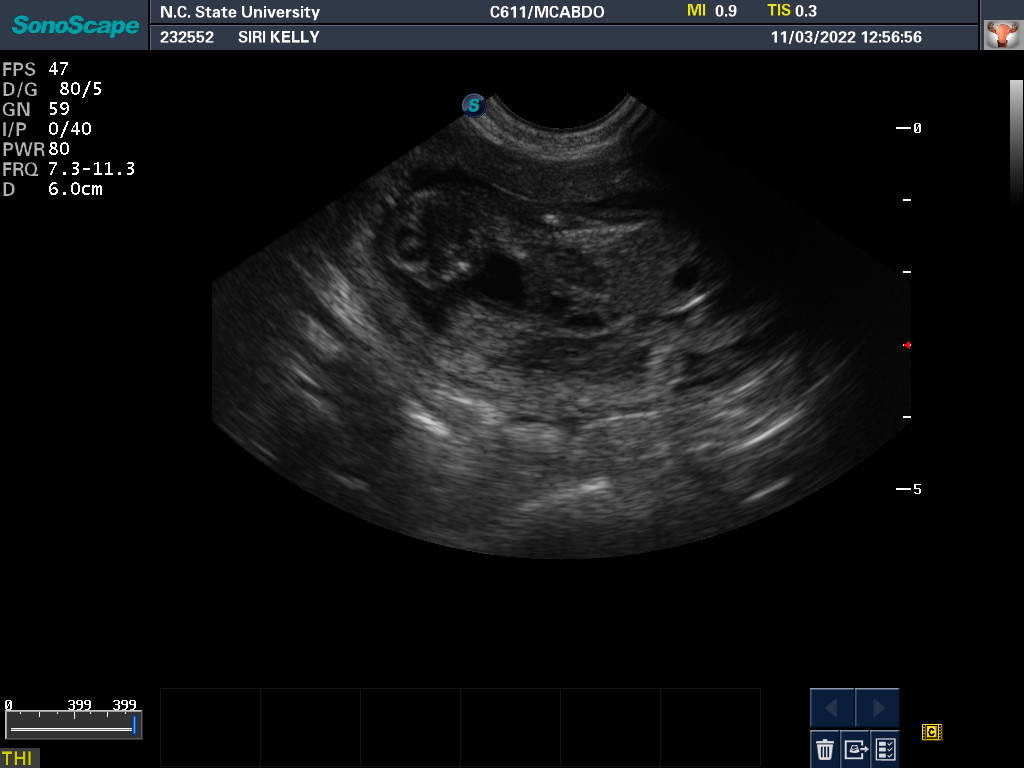

3 Nov 2022

Ultrasound today by the theriogenology (reproduction) veterinarians at NC State University showed that Siri is pregnant with possibly two puppies. It is difficult to accurately count puppies using ultrasound.

If all goes well, puppies are due around 28 November.